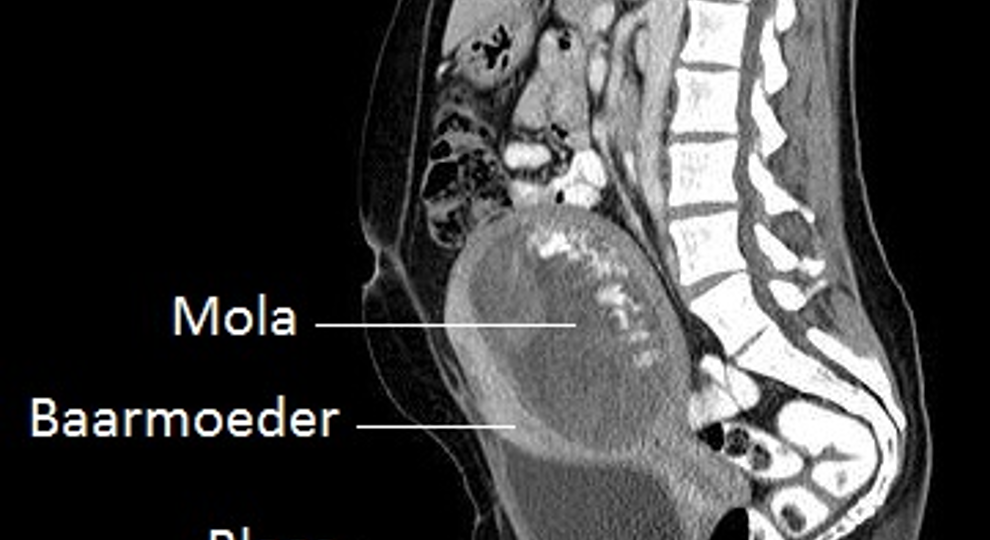

Hiernaast ziet u een voorbeeld van een CT-scan die een mola-zwangerschap laat zien.

De afkorting CT staat voor 'Computer Tomogram'. De CT-scanner werkt met dezelfde röntgenstralen als bij een 'gewone' röntgenfoto.Alleen maakt de CT-scanner dwarsdoorsneden van het lichaam, waardoor de arts als het ware plakjes van het lichaam kan zien. Als alle gefotografeerde plakjes achter elkaar worden gelegd, ontstaat een driedimensionaal beeld.